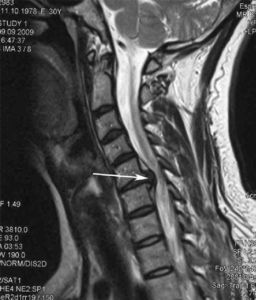

Видно ли грыжу позвоночника на рентгене

При выполнении рентгена позвоночника в двух проекциях (прямая, боковая) пациента спрашивают, видно ли межпозвонковую грыжу на снимке. Расстроим читателей, так как через хрящевую ткань лучи проходят без отражения, поэтому не визуализируются на рентгенограмме. На рентгеновском снимке четко прослеживаются тела позвонков, но между ними в местах локализации межпозвонковых дисков наблюдается «пустое» пространство. В этом месте располагается грыжа позвоночника. Квалифицированный врач-рентгенолог по косвенным признакам может определить вероятность разрушения фиброзного кольца и выпадения межпозвонкового диска за пределы тел позвонков. Сильное смещение сопровождается нарушением горизонтального положения замыкательных пластинок близлежащих позвонков пораженного сегмента. Щель приобретает косую направленность. Признак косвенный, поэтому рекомендуется назначение дополнительных методов обследования, которые позволят верифицировать причину патологии – компьютерная, магнитно-резонансная томография.

Мешотчатое выбухание пищевода может быть признаком дивертикула. При контрастной рентгенографии прослеживается выбухание слизистой оболочки на уровне глоточно-пищеводного отверстия, бифуркации трахеи, дуги аорты. Дискинезии пищевода проявляются избыточными сокращениями (спазмы), недостаточностью кардиального сфинктера. Расстройства визуализируются при контрастной гастроскопии. При патологии прослеживается гастроэзофагеальный рефлюкс, при котором пища из желудка забрасывается обратно в пищевод. Состояние способствует формированию грыжи пищеводного отверстия диафрагмы за счет расширения пищевода. При поддиафрагмальной, аксиальной грыже в грудную полость смещается кардиальная часть желудка. Через поддиафрагмальный сегмент в грудную клетку может выходить кишечник. Для определения видно ли грыжу диафрагмы на вашем рентген снимке предлагаем консультацию квалифицированных специалистов. Наши врачи-рентгенологи сформируют профессиональное альтернативное мнение. Грыжа позвоночника в шейном отделе (отмечена стрелкой)